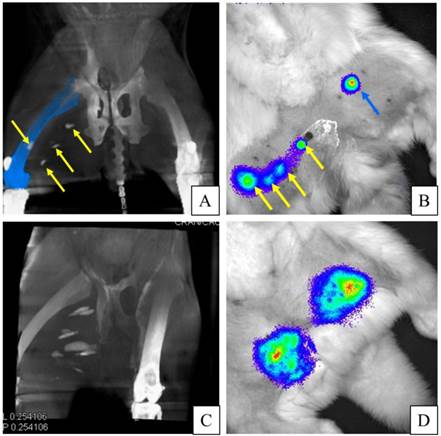

Figure 8

A: C-arm CT image demonstrates the visualization of PFOB-TF-MSCs injections (yellow arrows) in the right hind leg. (Femur is recolored blue to enhance visibility of one injection site.) B: In the same rabbit as in A, targeted luciferin injections 24 hours post transplantation reveal viable PFOB-TF-MSCs in the right thigh (yellow arrows) that correspond to c-arm CT and only one visible injection site of APA-TF-MSCs after non-targeted injections of luciferin into the left thigh (blue arrow). C: C-arm CT image of another animal showing PFOB-TF-MSCs injection sites in the medial thigh of right hindlimb. D: BLI of the same rabbit as in C dmonstrates one spot of viable PFOB-TF-MSCs in the left thigh and one spot of APA-TF-MSCs in the right thigh. Because of proximity of multiple injection sites, one cannot delineate the BL signal from each PFOB-TF-MSCs cluster. However, the multiple peaks in the signal intensity suggest that they are superposed.